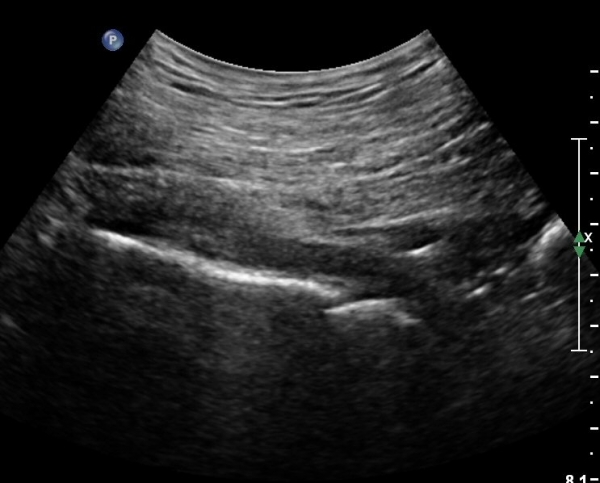

ÈÄ»óÀå°ñ±Ø ¿ÜÃø¿¡ ŽÃÊÀÚ¸¦ ¼öÆòÀ¸·Î ´ë¸é ½ÉÃþÀ¸·Î Àå°ñÀÌ °üÂûµÇ°í Àå°ñ Ç¥Ãþ¿¡ ´ëµÐ±Ù°ú ÁߵбÙÀÌ °üÂûµÈ´Ù(»çÁø 1).

ŽÃÍÀÚ¸¦ ´Ù¸®ÂÊÀ¸·Î ¼öÆò À̵¿ÇÏ¸é ½ÉÃþ¿¡¼­ Àå°ñÀÌ »ç¶óÁö°í »õ·Î¿î ±ÙÀ°ÃþÀÌ º¸À̴µ¥ À̰ÍÀÌ ÀÌ»ó±ÙÀ̰í ÀÌ»ç±Ù ½ÉÃþ¿¡¼­ Á°ñ½Å°æ¸£ °üÂûÇÒ ¼ö ÀÖ´Ù(»çÁø 2, 3).